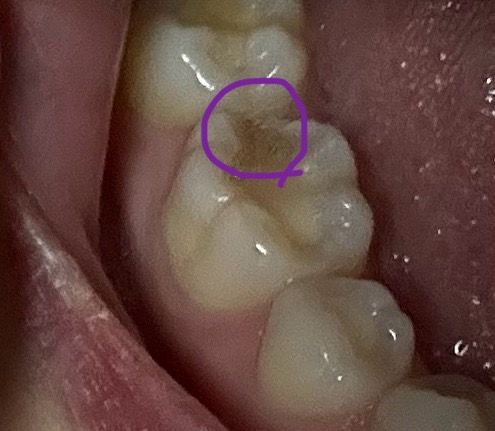

레진 좀 늦게하면 어떻게 되나요???

2010년 충치 레진 치료한게

깨졌는데 지금 당장 치과를

갈 수 없을 때.....

한 3주는 걸릴 것 같은데요..

늦게하면 큰일날까요?

그리고 3주간 어떻게 관리해야 할까요ㅠㅠ

• 1번 째 사진

3주동안 레진이 깨진상태로 방치시에 추가적인 파손 및 감염의 우려가 있습니다. 특히 충치가 있는 부위가 노출되면 세균이 쉽게 침투해 충치가 더 악화되거나 치아 신경에 영향을 줄 수 있습니다.

가능한 빠른시일내에 치과 방문을 하여 치료 받길 권하며, 해당부위에 음식물 찌꺼기가 남지 않도록 양치를 꼼꼼히 하여 관리하고, 소독용 헥사메딘 가글액으로 가글하여 균이 번식하지 않도록 관리하여주길 권합니다.